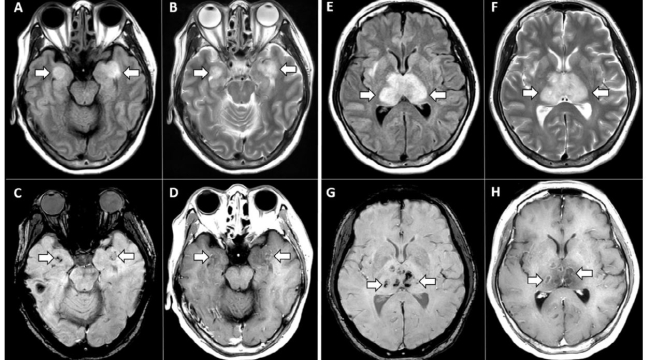

Bilim adamları, Covid-19 virüsünün zihinsel işlev üzerindeki endişe verici etkisini vurgulayan bir çalışma yayınladı. Buna göre hafif bir vaka bile beyne zarar verebiliyor ve fonksiyonlarını zorlaştırabiliyor. Araştırmacılar, kokuyla bağlantılı bölge de dahil olmak üzere enfeksiyondan aylar sonra Covid-19 ile ilişkili beyin hasarı ve on yıllık normal yaşlanmaya eşdeğer boyutta küçülme tespit etti. Pazartesi günü Nature dergisinde yayınlanan çalışmada, değişikliklerin bilişsel gerilemeyle bağlantılı olduğu aktarılıyor.

Beyindeki değişiklikleri araştırmak için sinirbilimci Gwenaelle Douaud ve meslektaşları dünyanın en büyük manyetik rezonans görüntüleme veri tabanından yararlandı. 785 gönüllünün beyinlerinin ilk MRI taramaları, yarım milyon insan için büyük ölçekli genomik verileri ve ayrıntılı klinik verilerini birleştiren çalışma Birleşik Krallık Biobank araştırmasının bir parçası olarak gerçekleştirildi.

Pandemi öncesi veriler ile ortalamada 38 ay sonrasının verileri karşılaştırıldı. O zamana kadar 401 katılımcının Covid-19 testi pozitif çıktı. Enfekte olmayanlar yaş, cinsiyet, kan basıncı, obezite, sigara, sosyo-ekonomik durum ve diyabet dahil olmak üzere birçok risk faktörü açısından hayatta kalanlara benzer bir kontrol grubu görevi gördü. 51-81 yaşları arasındaki bu kişiler yakından takip edildi.

Araştırmacılar, ikinci taramalarından ortalama 4,5 ay önce enfekte olanların beynindeki kokuyla ilişkili bölgelerde, orbitofrontal korteks ve parahipokampal girus olarak bilinen gri madde kalınlığında daha büyük bir azalma gözlemledi. Bu bulgu, doğrudan viral hasar veya vücudun virüse karşı bağışıklık tepkisi tarafından tetiklenen iltihaplanma sonucunda birçok Covid hastasının yaşadığı bozulmuş koku alma duyusunu açıklamaya yardımcı olabilir.

Melbourne'deki Florey Nörobilim ve Ruh Sağlığı Enstitüsü'nde nörofarmakolog Leah Beauchamp da "Beynin en dış katmanını oluşturan gri madde kaybı dejenerasyonu temsil ediyor. Bu gerçekten endişe verici." diyor. Enfekte grup ayrıca, enfekte olmayanlara kıyasla beyin boyutunda %0,2 ila %2 daha fazla küçülme yaşadı ve karmaşık görevleri üstlenen performanslarına bağlı olarak daha fazla bilişsel düşüş gösterdi. Bunun beyinciğin belirli bir bölümünde bilişle bağlantılı atrofi veya büzülme ile ilişkili olduğu tespit edildi. Enfekte ve enfekte olmayan katılımcılar arasındaki farkların yaşlı insanlarda daha belirgin olduğu da görüldü.

Araştırmacılar, ikinci taramalarından ortalama 4,5 ay önce enfekte olanların beynindeki kokuyla ilişkili bölgelerde, orbitofrontal korteks ve parahipokampal girus olarak bilinen gri madde kalınlığında daha büyük bir azalma gözlemledi. Bu bulgu, doğrudan viral hasar veya vücudun virüse karşı bağışıklık tepkisi tarafından tetiklenen iltihaplanma sonucunda birçok Covid hastasının yaşadığı bozulmuş koku alma duyusunu açıklamaya yardımcı olabilir.

Melbourne'deki Florey Nörobilim ve Ruh Sağlığı Enstitüsü'nde nörofarmakolog Leah Beauchamp da "Beynin en dış katmanını oluşturan gri madde kaybı dejenerasyonu temsil ediyor. Bu gerçekten endişe verici." diyor. Enfekte grup ayrıca, enfekte olmayanlara kıyasla beyin boyutunda %0,2 ila %2 daha fazla küçülme yaşadı ve karmaşık görevleri üstlenen performanslarına bağlı olarak daha fazla bilişsel düşüş gösterdi. Bunun beyinciğin belirli bir bölümünde bilişle bağlantılı atrofi veya büzülme ile ilişkili olduğu tespit edildi. Enfekte ve enfekte olmayan katılımcılar arasındaki farkların yaşlı insanlarda daha belirgin olduğu da görüldü.